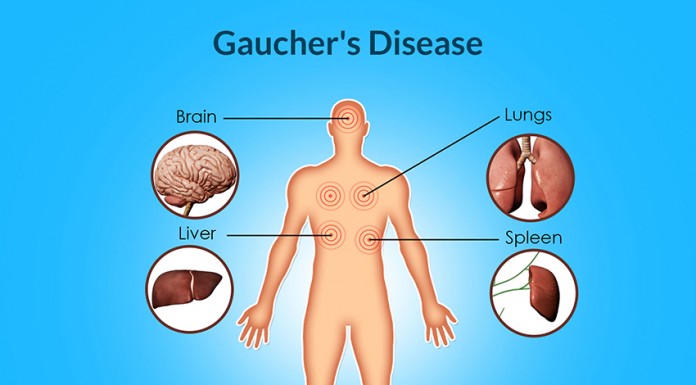

Diagnóstico pode ser feito com uma simples gota de sangue

A Dra. Tabita Magalhães Maia, Hematologista responsável pela consulta de Gaucher e do sector de...